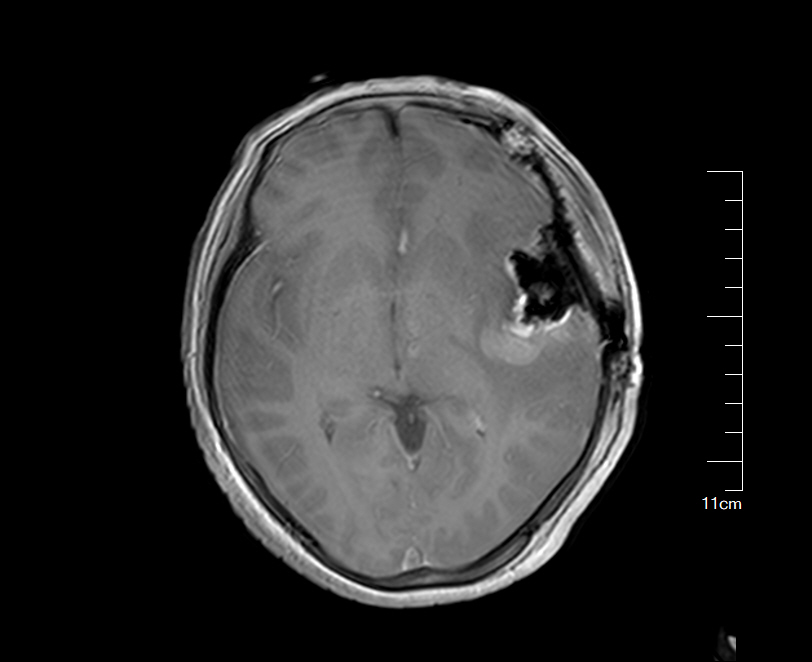

术中MRI提示瘤腔前内侧(额叶)残留肿瘤组织

残留肿瘤组织切除完全